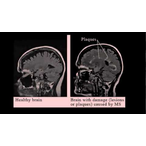

Multiple sclerosis